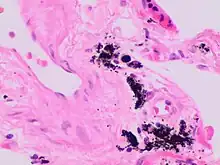

Micrograph of the spleen showing darkly stained, spheroid Gamna-Gandy bodies (arrows) outside the vessel wall at the center. Also shown is diffusely scattered, brown, granular hemosiderin pigment (arrowheads), indicating previous hemorrhage (hematoxylin & eosin staining, 40x magnification).

Gandy–Gamna nodules or Gandy-Gamna bodies, sometimes known as Gamna-Gandy bodies or Gamna-Gandy nodules, are small yellow-brown, brown, or rust-colored foci found in the spleen in patients with splenomegaly due to portal hypertension,[1] as well as sickle cell disease. They consist of fibrous tissue with haemosiderin and calcium deposits, and probably form due to scarring at sites of small perivascular haemorrhages.[2] They are visible on MRI scanning due to the presence of haemosiderin.[3]